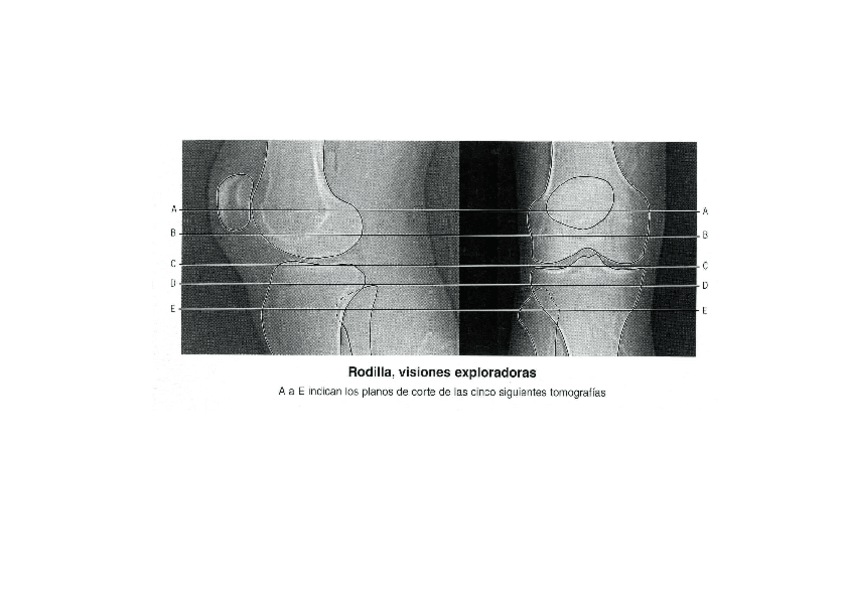

rodilla

He publicado nuevos apuntes de Técnicas de Tomografía Computarizada y Ecografía: rodilla

genoll-tc-Modo-de-compatibilidad.pdf